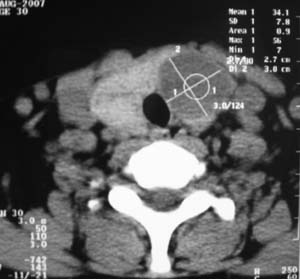

以下是引用zsl6918在2007-8-27 14:40:00的发言:[br]双侧甲状腺多发性低密度占位,边界清晰,密度欠均匀,尤以左侧明显,与周围组织分解清,考虑多发性腺瘤可能性大,不除外结节性甲状腺肿

以下是引用liaizhi在2007-8-27 15:20:00的发言:[br]双侧甲状腺散在多个囊性第密度影,左侧最大一个病灶与正常甲状腺分界尚可,气管受压稍右移。考虑甲状腺瘤的可能性大。